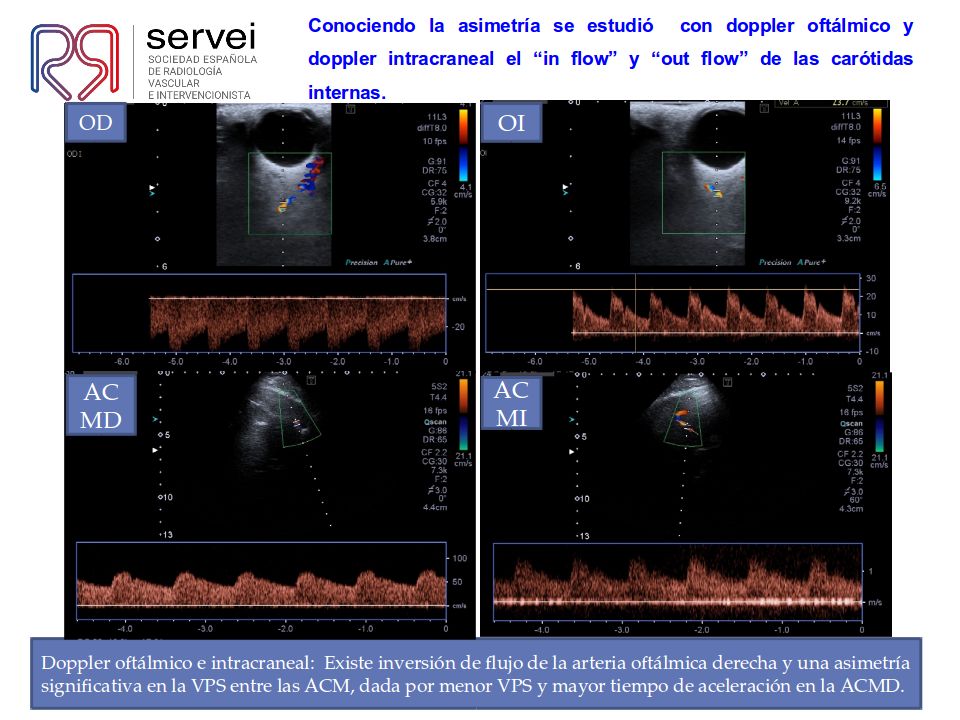

Doppler de TSA “La ausencia de aceleraciones, descarta patología…”